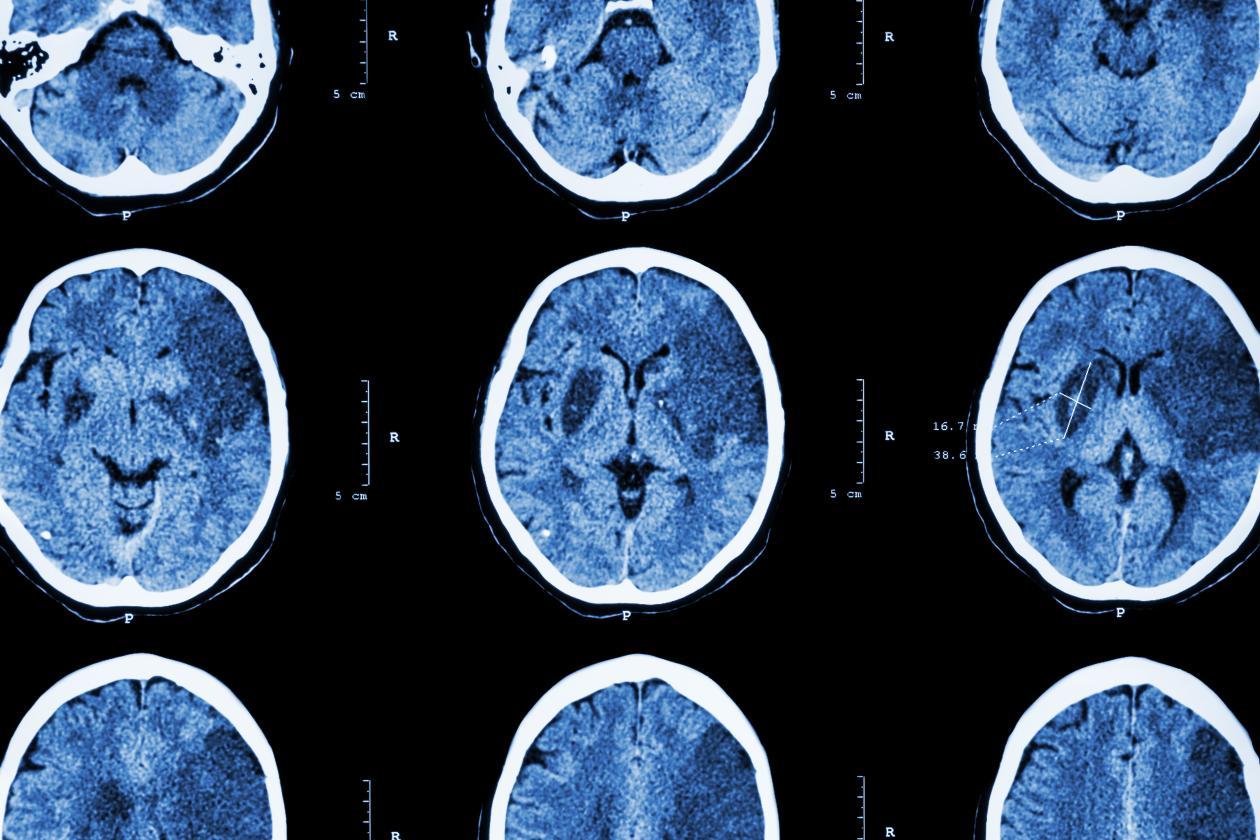

1.计算机断层扫描(Computed Tomography,CT):

原理:利用X射线穿透人体,通过计算机重建出断层图像,无须真实切割即可观察颅脑内部结构。

特点:扫描速度快(1~3分钟即可完成),非常适合神经科颅脑疾病紧急情况下的快速诊断,如急性脑出血、颅骨外伤等。

图1 版权图片 不授权转载